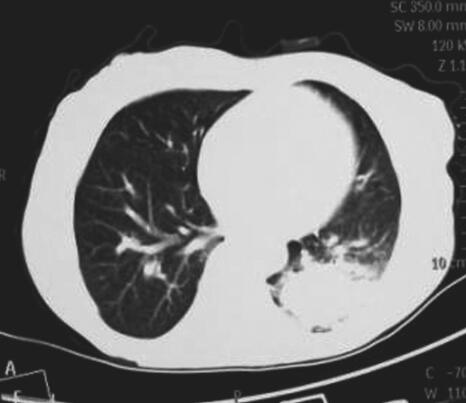

图4 肺部CT

右肺上叶阻塞性肺不张,左肺团块影,周围见片状渗出影,较前增大